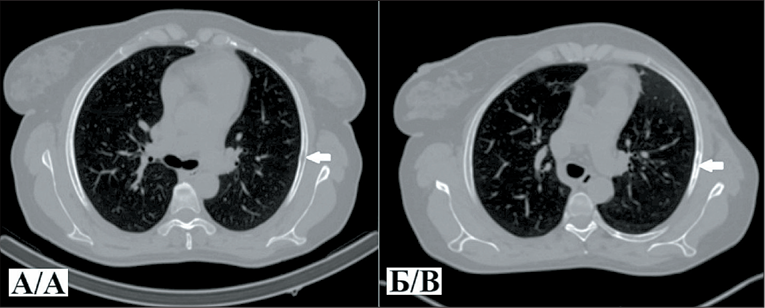

Клинический случай № 1. Пациентка К., 51 год, диагноз: Рак правой молочной железы, IIIC стадия (T2N3M0), мультицентричный рост, метастатическое поражение аксиллярных и подключичных лимфоузлов. ОФЭКТ/КТ выполнена через 2 ч после внутривенного введения РФЛП [99mTc]Tc-DB8 в дозировке протеина 80 мкг. По результатам исследования помимо первичной опухоли и метастатических лимфоузлов выявлен высокий уровень аккумуляции препарата [99mTc]Tc-DB8 в проекции V ребра справа по средней аксиллярной линии. Повторный анализ компьютерных томограмм органов грудной клетки (КТ ОГК) подтвердил наличие очага литической деструкции, расцененного как возможный метастаз и взятого под наблюдение. При КТ ОГК в динамике в указанной проекции визуализировался участок неравномерных склеротических изменений, что интерпретировано как ответ на терапию.

2. Рис. 2. А – компьютерная томография органов грудной клетки в аксиальной проекции (костное окно) больной К. до лечения (белой стрелкой указан участок литической деструкции в V ребре по средней аксиллярной линии справа, размером 19×5 мм); Б – исследование через 11 мес после лечения (белой стрелкой указан участок неравномерных склеротических изменений в V ребре по средней аксиллярной линии справа, размером 26×5 мм). Примечание: рисунок выполнен авторами